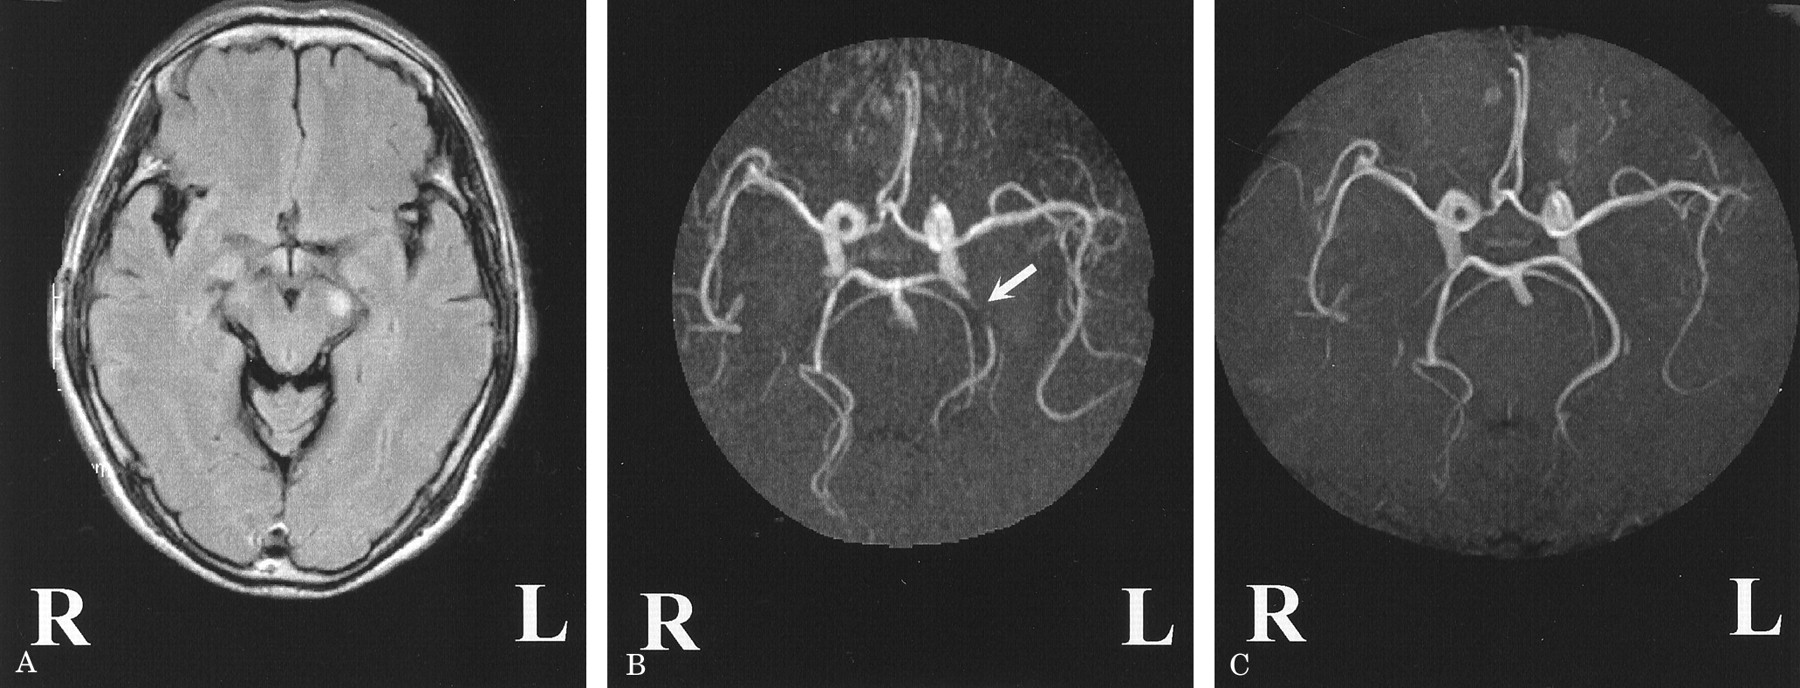

一个65岁的老人与高血压发达轻微程度的构音障碍和右手的疲弱。神经系统检查显示中央麻痹性痴呆的右脸,舌头,上肢无共济失调。Fluid-attenuated反转恢复成像(1.5特斯拉,日立医疗层云II)显示标记hyperintensity信号在左大脑脚(图,一个)。先生血管造影术(MRA),使用一个三维飞行时间序列,披露违规左侧基底动脉狭窄的环境(P2)段(见图B岁),与之前相比MRA(参见61年图中,C)。

图。(一)轴向fluid-attenuated反转恢复成像。(B)崩溃成像的大脑血管成像(MRA)显示狭窄左先生P2段(箭头所指)。(C)崩溃以前大脑血管摄影的成像。

腔隙性梗死大脑脚很少发生,可能导致dysarthria-one-hand弱点。1大脑脚的循环是由沟通后的穿支动脉和花梗的穿通动脉和大脑后动脉弯曲的树枝。那些射孔和圆周分支源自precommunical (P1)或P2的大脑后动脉。2我们的图片表明身体的同侧的P2的狭窄段可能导致脑花梗的梗死病人。